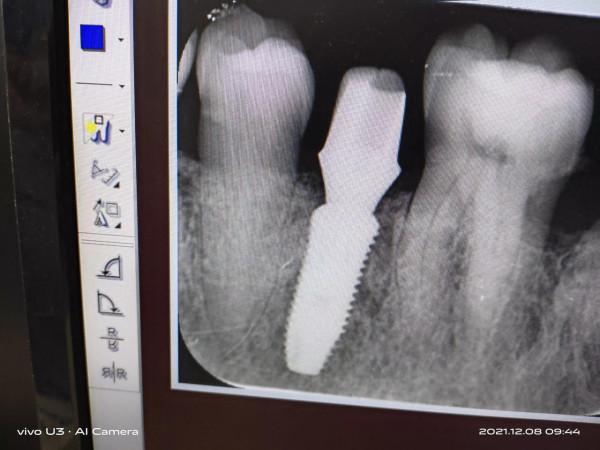

10月22日已是六個月後了,通知去醫院做基臺,這才看到給我做手術的院長了(從聲音辨別出來的),反覆清洗試裝,沒有痛苦和不適的感覺,四十分鐘就完成了,看下圖

圖中可以看出植入體和牙骨結合以上是我的種植牙的過程和體會希望能對種植牙抱有困惑的人有所幫助。